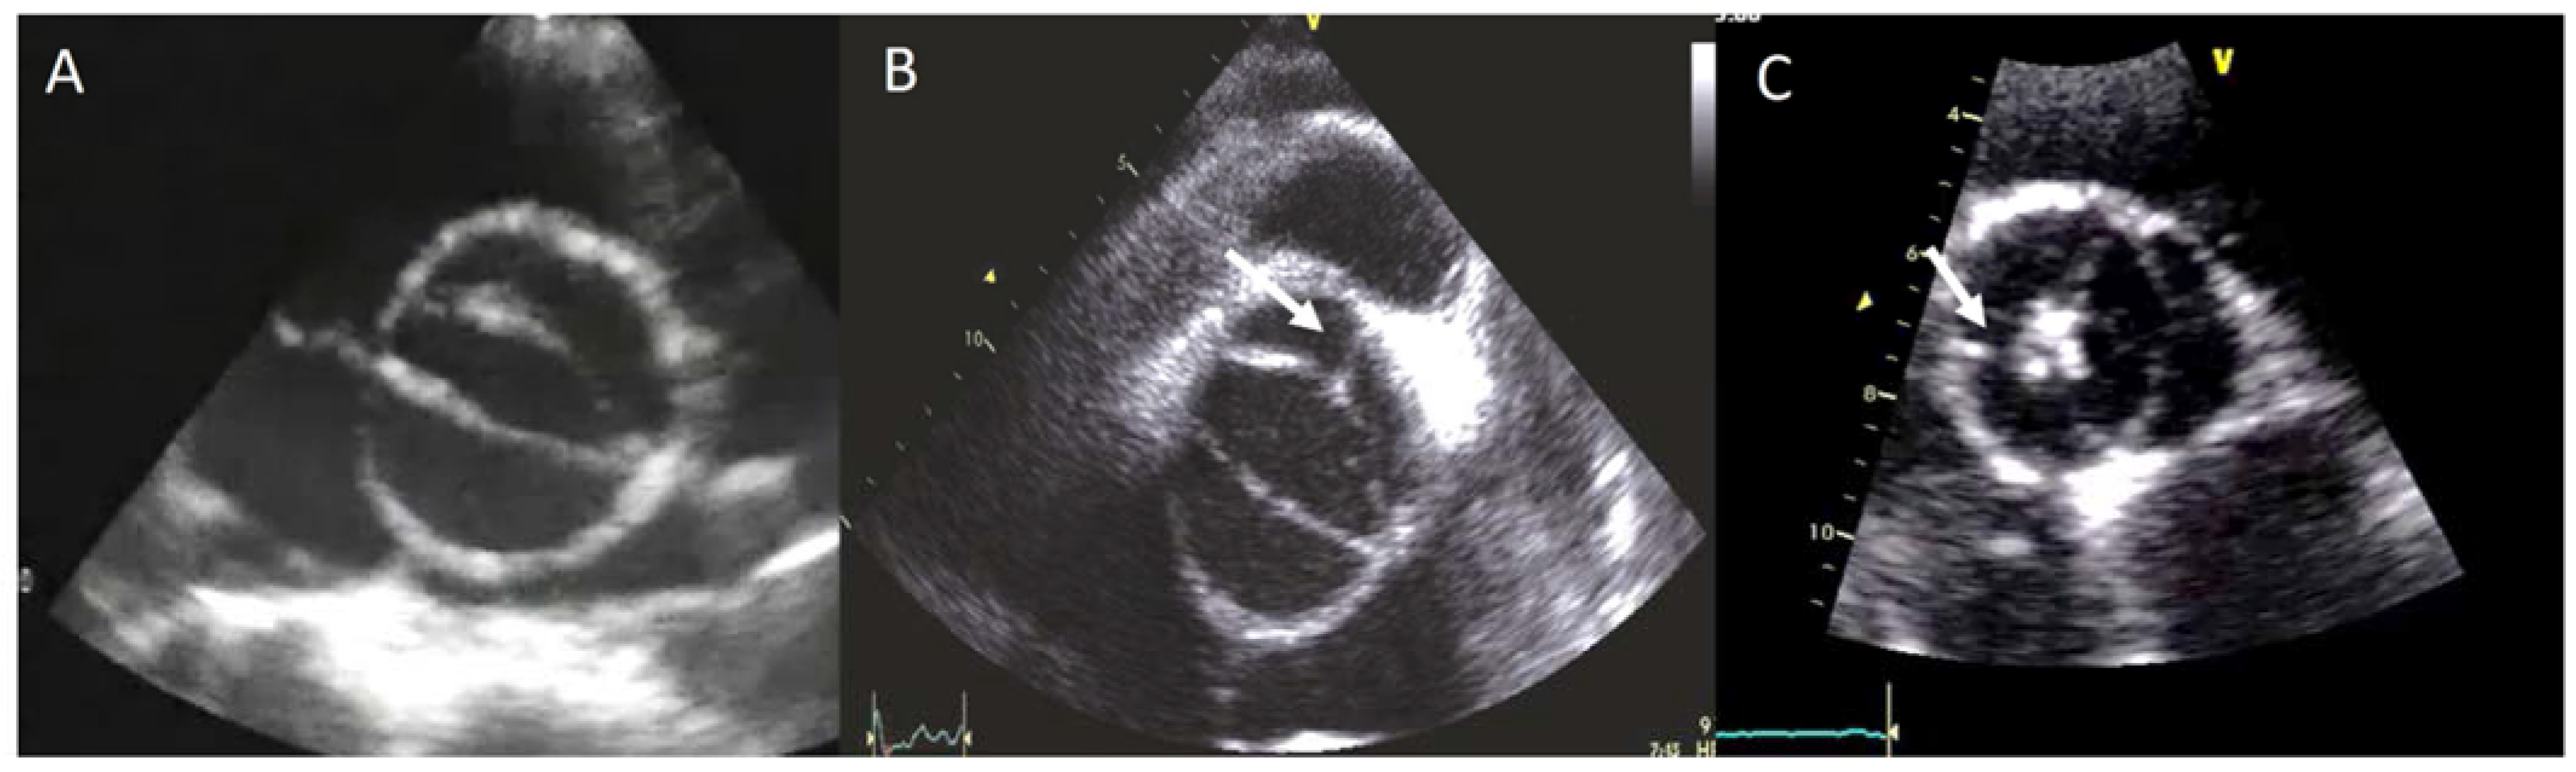

The BAV phenotypic expression represents an anatomic continuum of increasing non-fused cusp commissural angles and increasing similarity of cusp size and shape. This spectrum goes from the partial-fusion BAV (very near to a tricuspid aortic valve) to other phenotypes such us those asymmetric fused, symmetric fused phenotypes with and without a raphe, and finally to the two-sinus BAV, which is considered the most severe defect and is anatomically close to perfect “bicuspidity” [19]. The best view of the phenotype BAV is the TTE parasternal short-axis or its equivalent in TEE, CT, or CMR (Figure 1).

Figure 1.

Most frequent types of BAV by TTE. (A) BAV without raphe type antero−posterior; (B) RC−LC fusion with raphe (arrow); (C) RC−NC fusion with raphe (arrow).